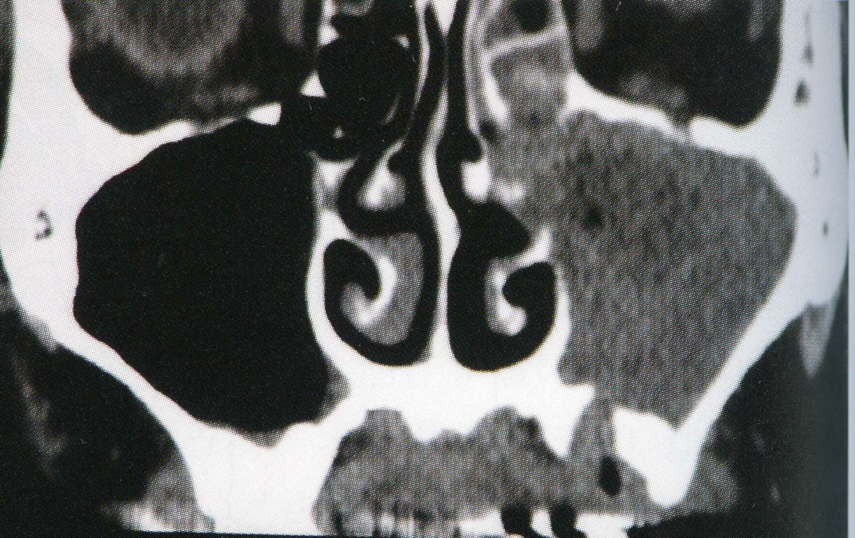

歯性上顎洞炎

左側上顎洞内に不透過像を認める。